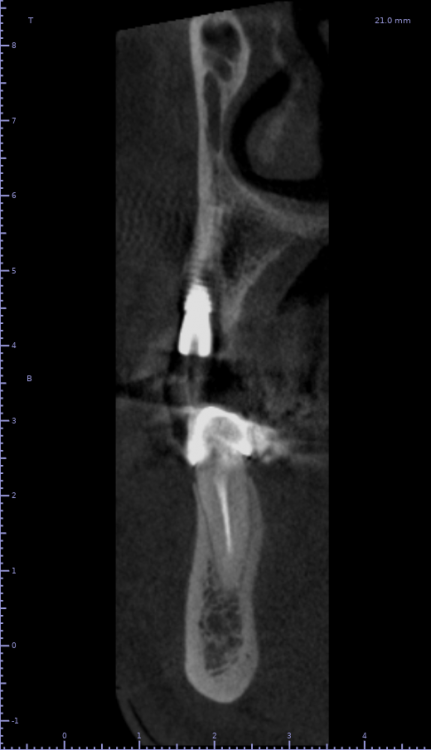

Женька Опубликовано 19 апреля, 2021 Автор Поделиться Опубликовано 19 апреля, 2021 Rg Ссылка на комментарий

Женька Опубликовано 21 июля, 2021 Автор Поделиться Опубликовано 21 июля, 2021 3 месяца минуло... клык на торке 30 неприятные ощущения второй премоляр на 10 и подвижность... отправил на кт. Всё насмарку... Ссылка на комментарий